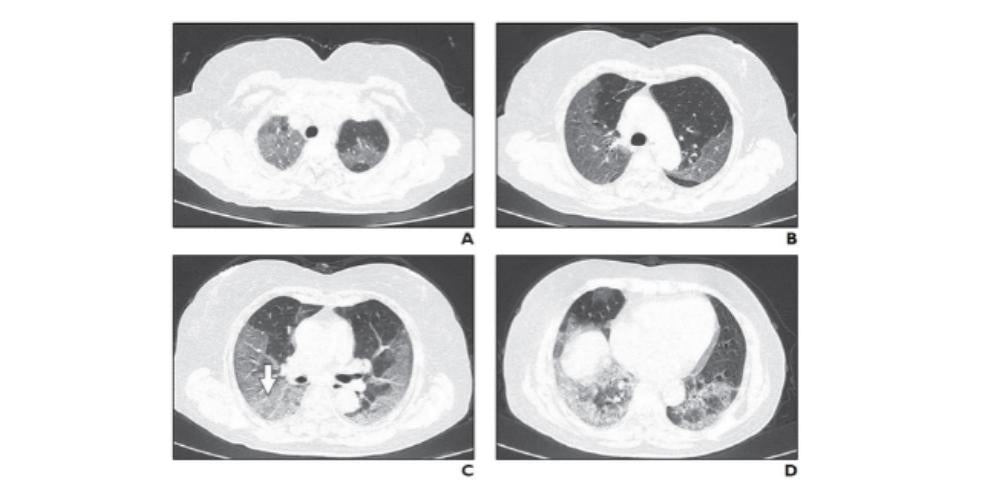

- COVID-19 pneumonia’s appearance is usually ground-glass opacities or peripheral consolidation on chest x-ray and CT

For example, a patient with visible ground-glass opacities on CT or x-ray and who requires no oxygen at day 3 may display an extension of ground-glass opacities. By day 9, the patient could require oxygen, and by day 13 be experiencing respiratory distress and require hospitalization.